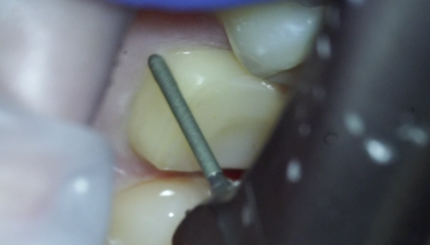

Препарирование 11 21

10 августа 2021